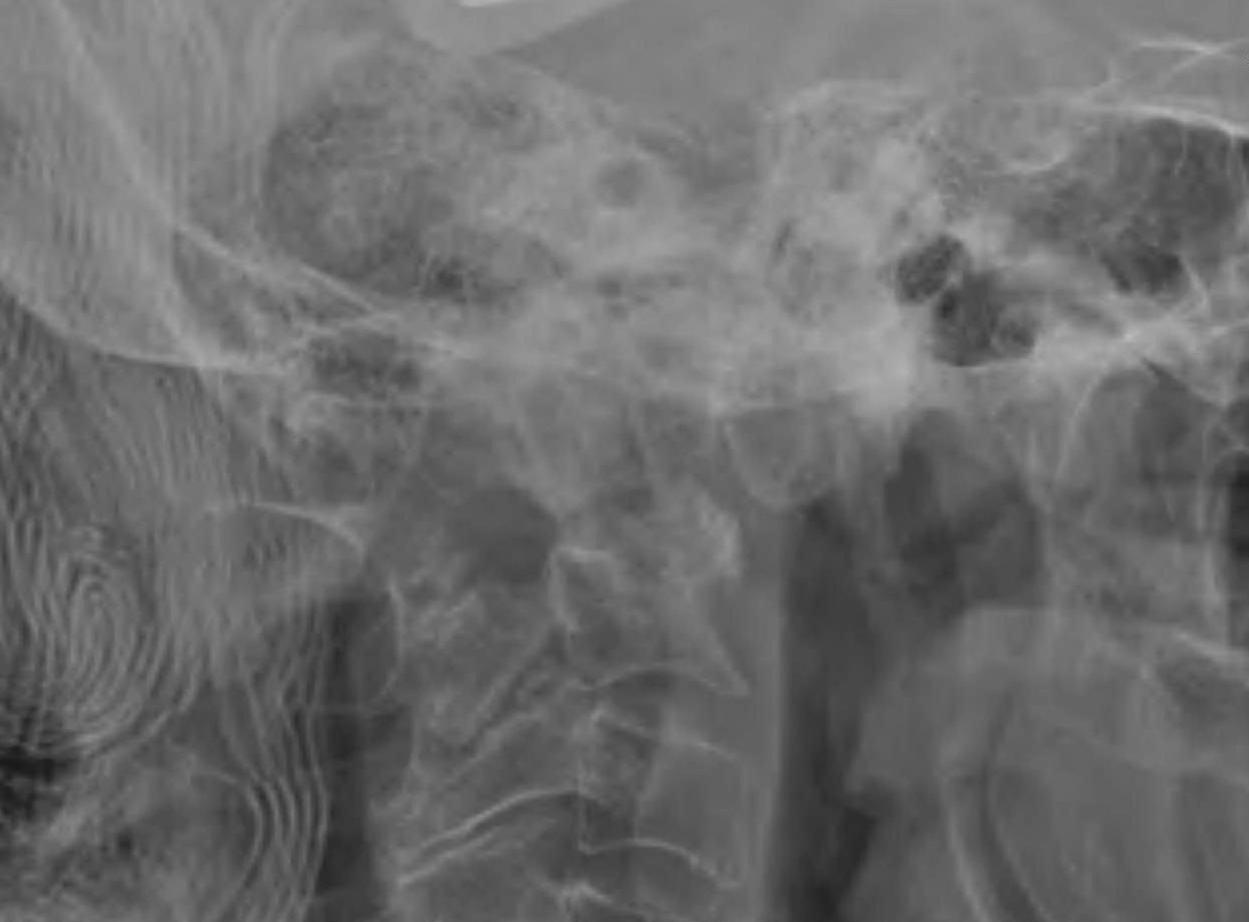

Pathology

Facet erosions / ligament incompetence

May see at multiple levels with stepladder type deformity & kyphosis

Can occur beneath previous cervical fusions including C1/C2

MRI

Management